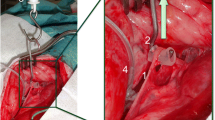

First, the cranial part of the RLN was placed on a piece of foam to electrically insulate it from the surrounding tissue. Then, needle electrodes (Dr. Langer Medical GmbH) were inserted through the nerve into the foam, while the grounding electrode was introduced into a nearby muscle. A saxophone electrode (Dr. Langer Medical GmbH) was attached caudally to the needle electrodes. Next, the electrodes were connected to the neuromonitoring device (AvalancheXT Neuromonitor © Dr. Langer Medical GmbH), and the saxophone electrode stimulated the nerves with 1 Hz pulses at 0.5—5 mA (Fig. 1). An initial baseline assessment of the electrophysiological properties of the nerve was performed. If the nerve displayed no response to electrical stimulation, it was discarded, and the contralateral side was dissected. However, if the nerve did respond to electrical stimulation, the baseline signal parameters of amplitude, latency, threshold current, and supramaximal voltage were determined. The latter two parameters were established by starting nerve stimulation at 0.1 mV and gradually increasing the stimulation in 0.1 mV increments. Subsequently, the nerve was positioned on a spring scale midway between the saxophone electrode and the needle electrodes, applying tensile forces between 0.5 N – 2 N for sixty seconds.